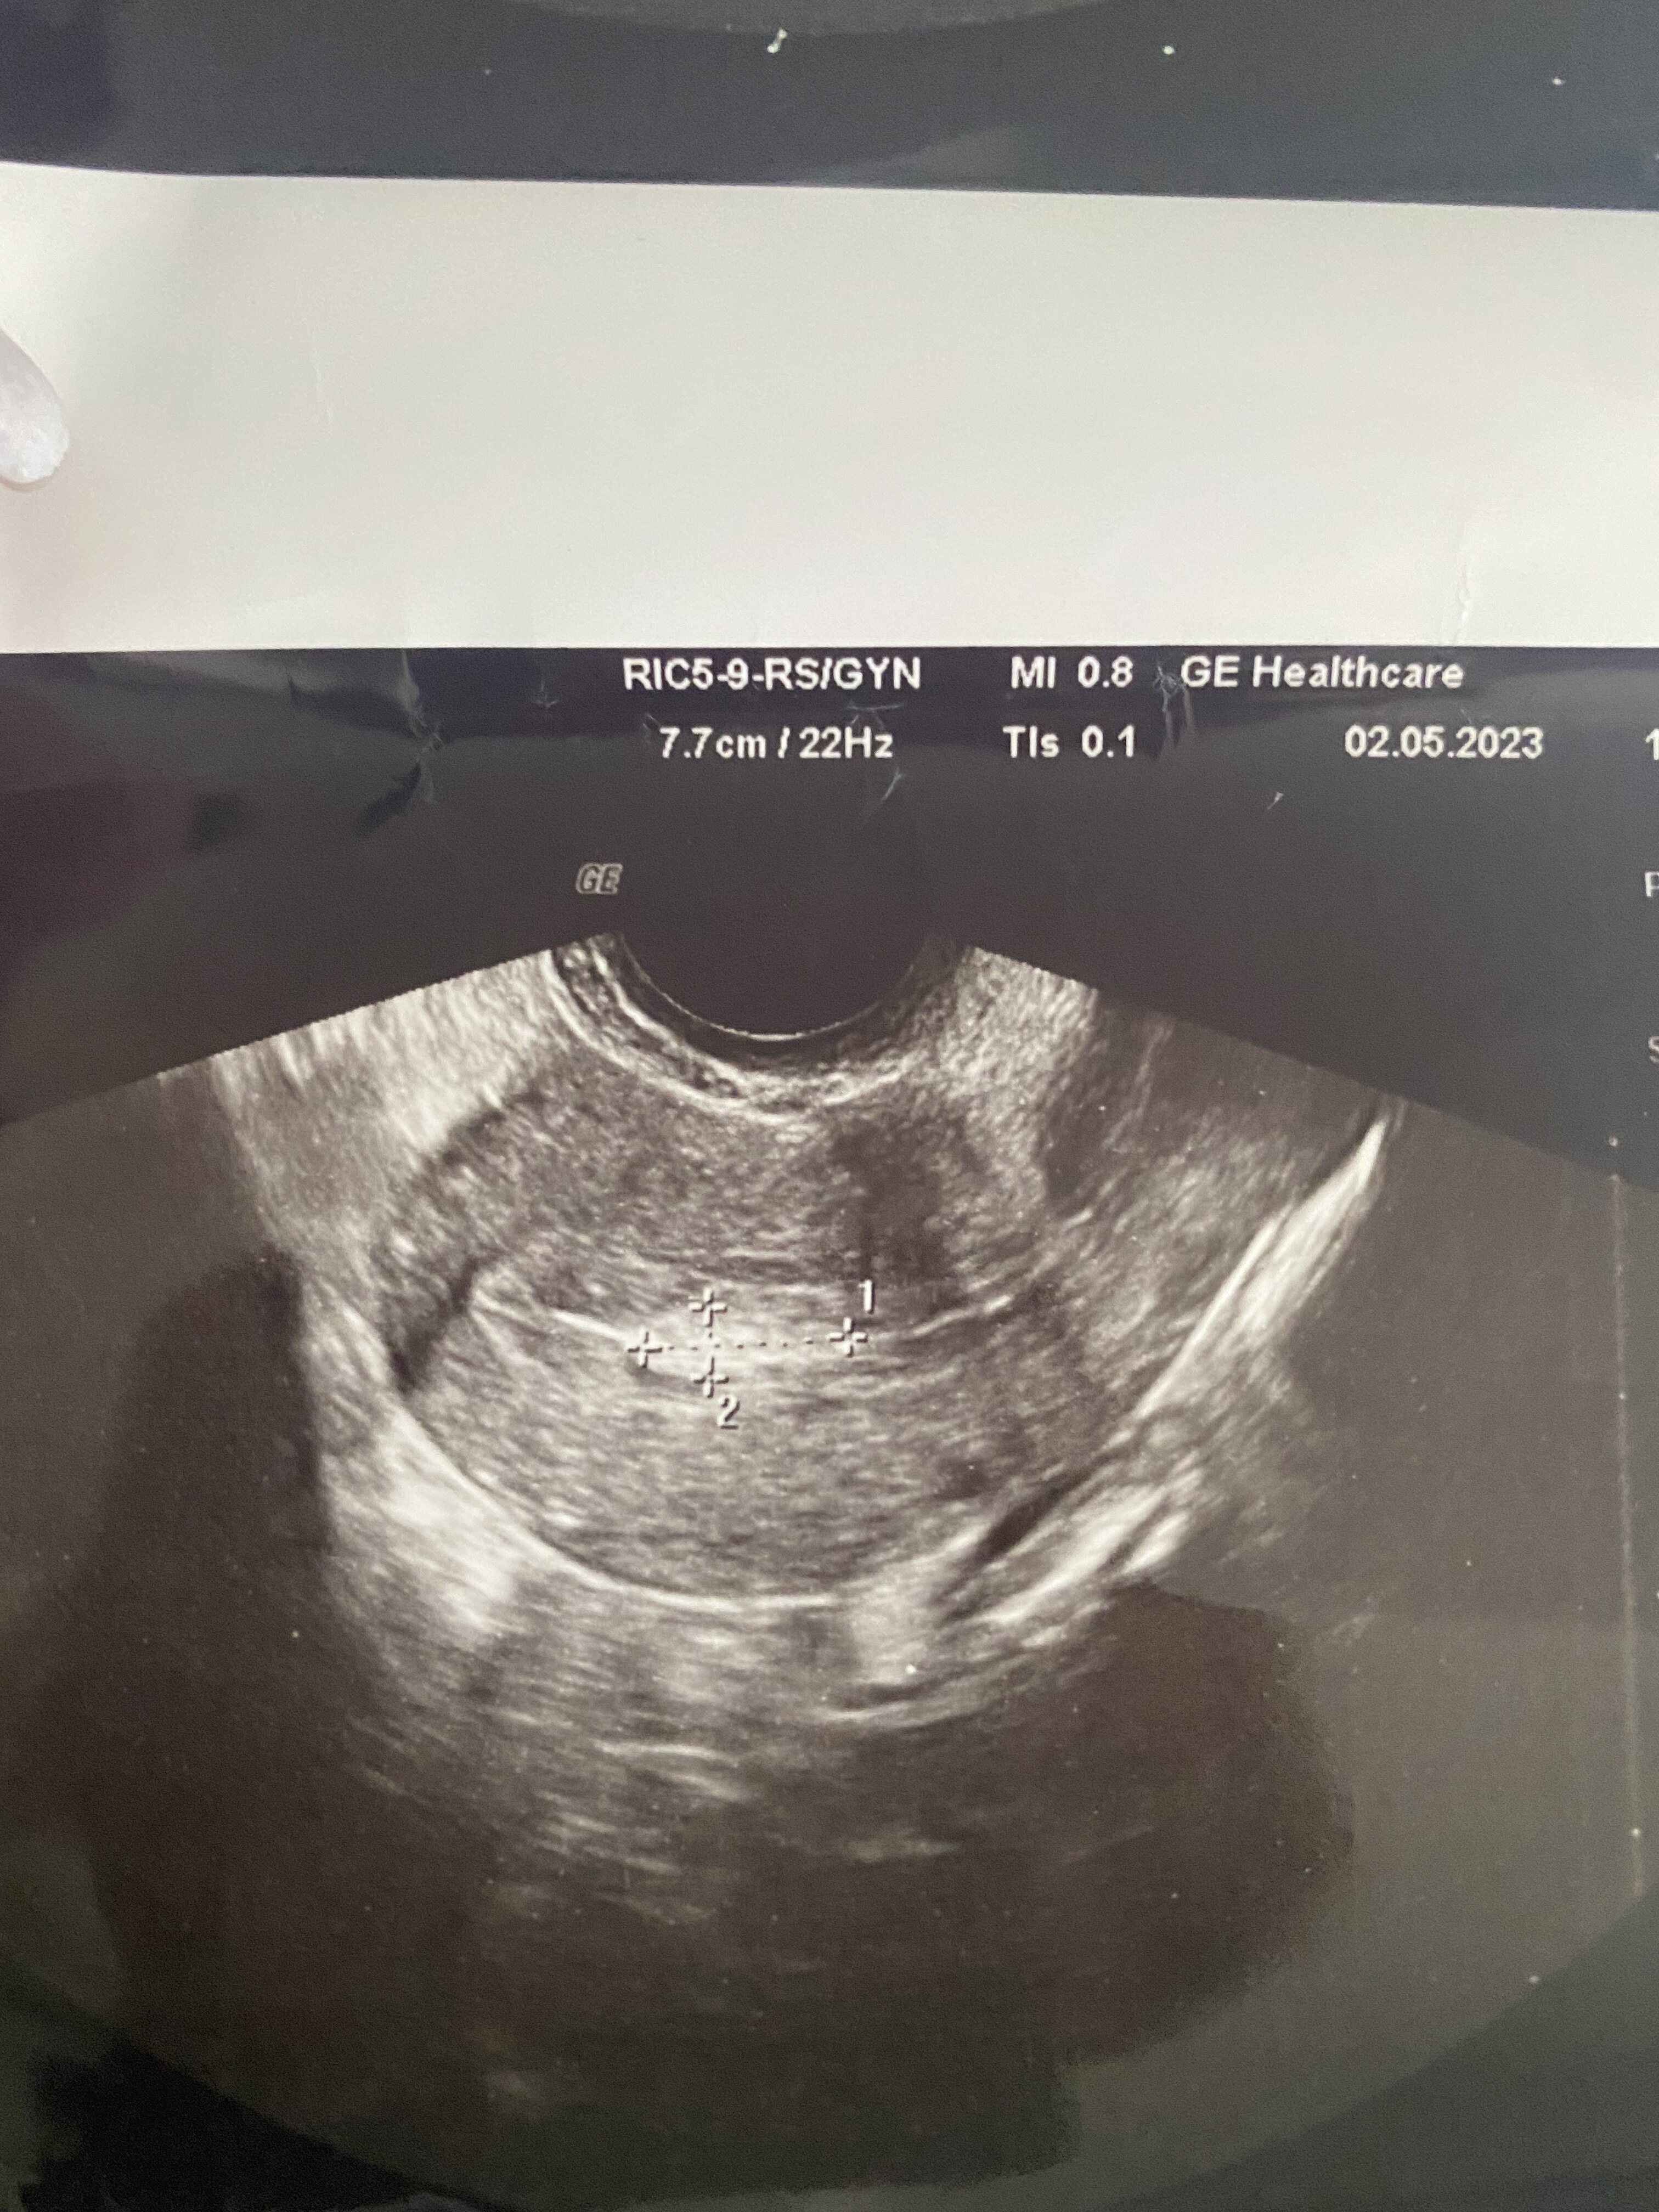

Na początku roku podjęliśmy wspólnie z narzeczonym decyzje ze zaczynamy sie starać o bobasa. Poszłam do ginekologa z nadzieja na zielone światło a dostałam kubeł zimnej wody a mianowicie wykrył u mnie polipy endometrialne- w jamie macicy.. nigdy wcześniej nie miałam wykrytych polipów u innych ginekologow ale chodziłam zazwyczaj w drugiej połowie cyklu i miałam ewentualny przerost endometrium tzn dość grube, zmieniłam ginekologa bo sie przeprowadziłam i od tego dostałam skierowanie do szpitala wlasnie przez te polipy. Histeroskopie miałam wykonana w marcu tego roku pod koniec cyklu bo akurst takie mieli wolne terminy… Miesiąc pozniej wizyta kontrolna u tego samego ginekologa. Jak sie okazało nie wszystko usunęli. Moj polip na ten moment ma 14 mm x 6 mm x4 mm endometrium 7 mm zaraz po okresie. Lekarz powiedział ze mamy sie starać ale nie robic za bardzo nadzieji a za 3 Msc na kontrole jak sie nie uda i zobaczyć czy polip sie nie powiększył. Mówił ze cos trzeba robić, zapisa luteinę 16-25 dc na podtrzymanie jeśli sie uda , mam cykle zazwyczaj Ok 29 dniowe. Pierwszy cykl starań póki co nadziei większych nie mam robiłam dzis test w 24 dc negatywny . Czy komuś udało sie zajść w ciaze z polipem? Czy konieczne bedzie usuwanie go po raz kolejny? :/

Mogę dodać jeszcze ze krwawiłam w tym cyklu raz na brązowo/ różowo w dzień owulacji i tydzień po niej tez miałam brązowy sluz na wkładce. Po za tym żadnych innych objawów, trochę sie naczytałam ze to moze implantacja ale 2 dni po plamieniy i w 9dpo test negatywny, dodam ze raczej nigdy nie plamien nie mam. Dołączam zdjęcie polipa.

• 3CA2F28D-23C8-4477-80AC-5C8908200FD2.jpeg